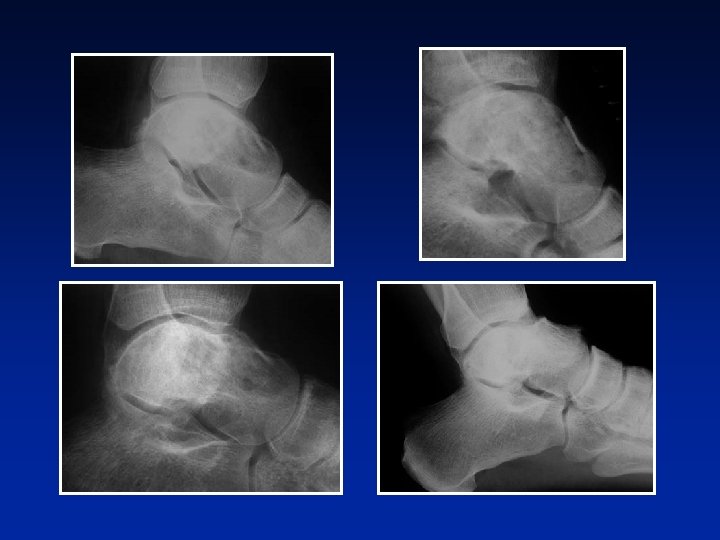

TUMOR DE CELULAS GIGANTES Evolución Tumor benigno (? ) maligno (? ) pronóstico incierto Complicaciones frecuentes: Recidivas frecuentes (50 %) Periodo de 5 meses a 20 años.

TUMOR DE CELULAS GIGANTES Evolución Tumor benigno (? ) maligno (? ) pronóstico incierto Complicaciones frecuentes: Recidivas frecuentes (50 %) Periodo de 5 meses a 20 años. Degeneración sarcomatosa (15 %)

TUMOR DE CELULAS GIGANTES Evolución Tumor benigno (? ) maligno (? ) pronóstico incierto Complicaciones frecuentes: Fracturas, pseudoartrosis, infecciones, compresiones nerviosas Recidivas frecuentes (50 %) Periodo de 5 meses a 20 años. Degeneración sarcomatosa (15 %) desde el inicio o luego de la radioterapia o luego de otros tratamientos Metástasis pulmonares

Tratamiento Curetaje extenso Buenos resultados Recidivas: 50 % de los casos

Tratamiento • Curetaje extenso + relleno Grado 2 Injerto a 13 años - recidiva a 31 años - injerto